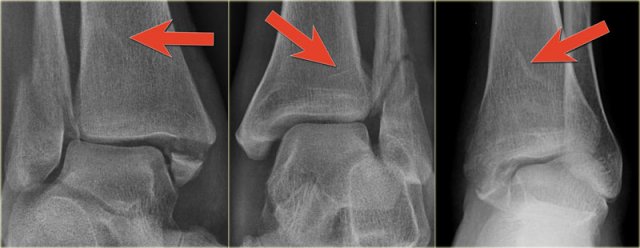

When we study the radiographs of a patient with an ankle injury, we have to study the region of the posterior malleolus very carefully.

In many cases there is only a small gap between the fracture parts and detection depends on optimal radiography and a high level of suspicion.

The images show an obvious Weber B fracture.

On the AP-view the linear lucency is the clue to a tertius fracture (red arrow).

It results from subtle malalignment of the fracture fragment.

Likewise in some cases malalignment can result in a linear density.